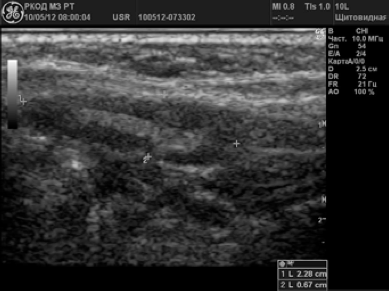

Ganglionii limfatici ai gâtului cu Chlamydia

Prevalau noduri formă rotunjită, P / PP<2,0 (84%). Большин-ство ЛУ (89,9%) были гипоэхогенными с гетерогенными внутренними эхосигналами, область ворот либо не дифференцировалась, либо была резко сужена. В допплеровских режимах в пораженных ЛУ определялся усиленный смешанный тип крово-тока с повышенной перфузией как в центре, так и по периферии ЛУ в 82,6% случаев.